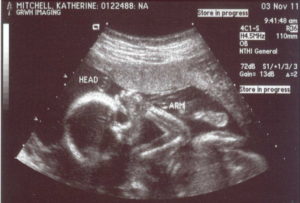

На протяжении всей беременности любая женщина ожидает очередное ультразвуковое исследование – именно тогда она может увидеть своего еще не родившегося малыша на мониторе аппарата и узнать его пол.

Но УЗИ при беременности этим не ограничивается, оно в первую очередь направлено на наблюдение за внутриутробным развитием плода и мамы и оценку полученной информации.

При получении результатов диагностики женщины могут задаваться вопросом – может ли УЗИ ошибаться?

Ультразвуковое исследование позволяет получить информацию о расположении плаценты, физическом состоянии плода и степени его развития, особенностях пуповины.

Несмотря на высокоинформативность и достоверность данного метода, те или иные погрешности имеют место.

Ошибочные результаты могут быть вызваны такими факторами, как устаревшая аппаратура, невысокая квалификация врача ультразвуковой диагностики, несвоевременность проведения УЗИ. Чаще всего ошибки ультразвукового исследования допускаются при определении: